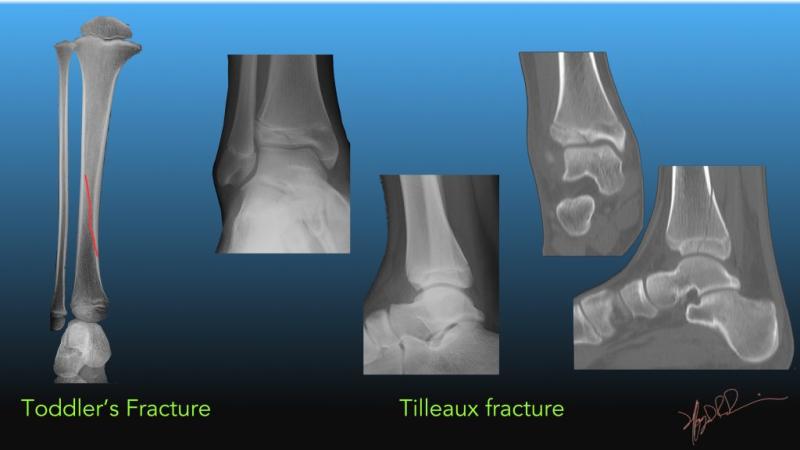

كسور وخلوع الكاحل والقدم عند الأطفال: أسبابها وعلاجها

الكاحل والقدم هما من أكثر الأجزاء التي تتعرض للإصابة عند الأطفال، خاصة في سن المراهقة. فالأطفال يمارسون العديد من الأنشطة الرياضية واللعبية التي تزيد من خطر حدوث كسور أو خلوع في هذه المنطقة. وفي بعض …